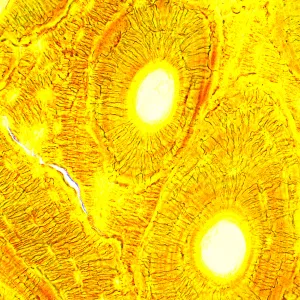

Биологический микроскоп MAGUS Bio 250T – профессиональный прибор для наблюдения биологических образцов в проходящем свете. Основным методом исследований является светлое поле – он доступен в комплектации «из коробки». Методы темного поля, поляризованного света и фазового контраста тоже могут использоваться, но для этого потребуется оснастить микроскоп опциональными аксессуарами. Микроскоп отлично подходит для лабораторных и научно-исследовательских наблюдений в медицине, фармацевтике, криминалистике, сельском хозяйстве и других областях науки.